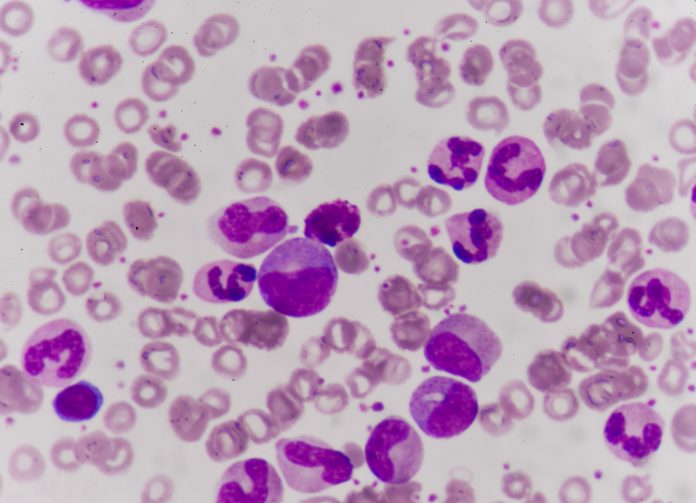

Diagnosing hereditary angioedema

Globally, an estimated one in 50,000 people are affected by hereditary angioedema, but due to its rarity, correct diagnosis is often challenging.